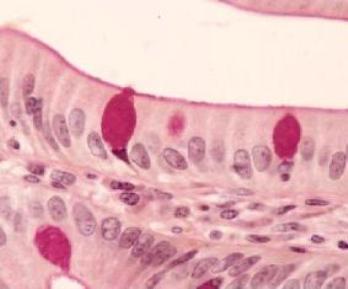

Célula caliciforme.PAS